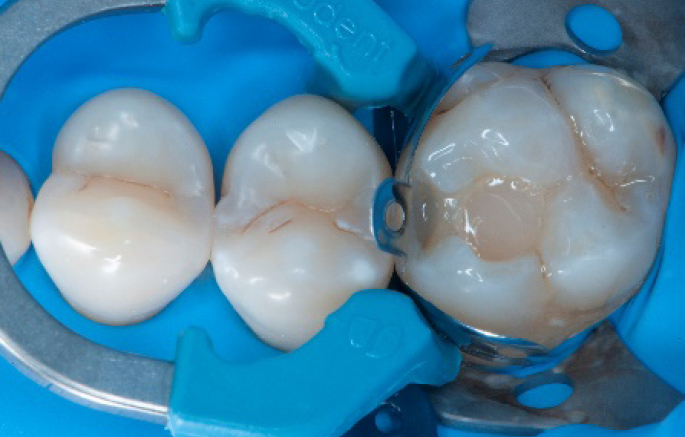

Step 4:

The complete Palodent1 system in place: sectional matrix, wedge and ring.

Step 8:

Transformation of class II into class I, restoring the interproximal wall with Spectra ST4 composite in shade A2.

Step 9:

Transformation of a big class I into a small class I, using SDR® Plus material in one increment up to 4 mm.

Step 10:

The situation after the application of SDR® Plus material.